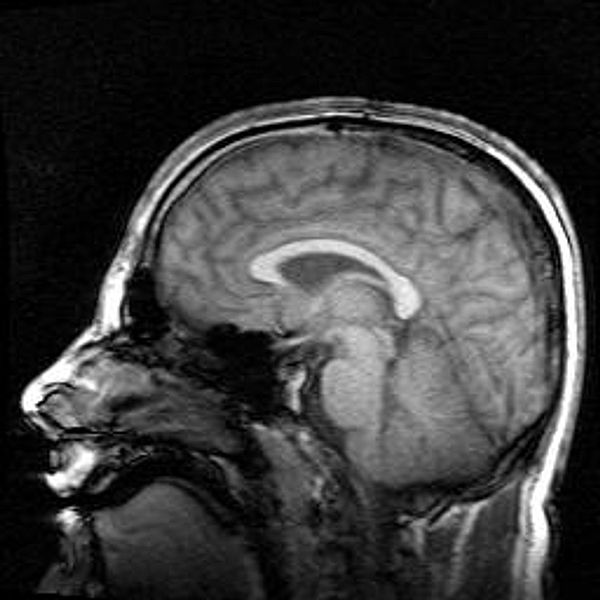

Image: Magnetic Resonance Imaging - Human brain sideview, by Oliver Stollmann, courtesy Wikipedia Commons